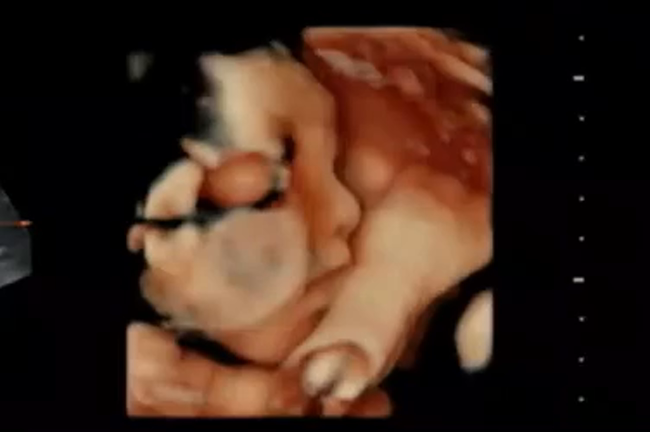

28w6d 妊婦健診⑦ 4D動画

2023年4月13日